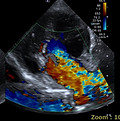

심장 질환

노령 반려동물에서 흔히 발생하는 이첨판 폐쇄부전증(MMVD), 확장성 심근병증(DCM),

비대성 심근병증(HCM), 부정맥, 심부전 등을

전문적으로 다룹니다.

심장초음파, 심전도 검사를 통해 조기 진단이 가능하며, 약물치료와 장기적인 모니터링으로 삶의 질을 유지할 수 있도록 돕습니다.